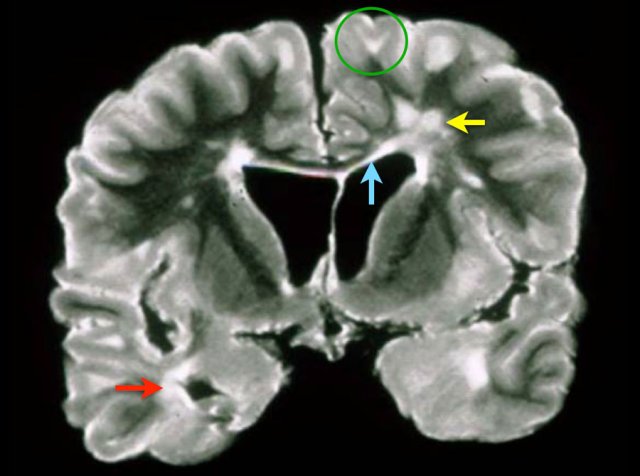

Spinal cord lesions

Typical spinal cord lesions in MS are relatively small and peripherally located.

They are most often found in the cervical cord and are usually less than 2 vertebral segments in length.

A spinal cord lesion together with a lesion in the cerebellum or brainstem is very suggestive of MS.

Spinal cord lesions are uncommon in most other CNS diseases, with the exception of ADEM, sarcoid, and NMOSD.

The images show multiple short-segment lesions in the spinal cord.

On PDW-images the spinal cord has a uniformly low signal intensity (like CSF), which gives the MS lesions a good contrast against the surrounding CSF and normal cord tissue.

Use a 512 matrix and cardiac gating for optimal results.

A good alternative for PDW is STIR.

Make sure to have two different sequences or two different planes.